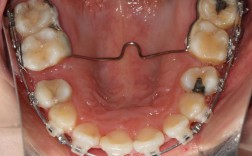

(图片来源网络,侵删)通过更换结扎丝(如不锈钢丝结扎、弹性结扎圈)改变托槽与弓丝的紧密度,增强摩擦力或允许牙齿滑动,例如滑动法关闭间隙时需结扎丝宽松,而需要精细控制时需紧密结扎。